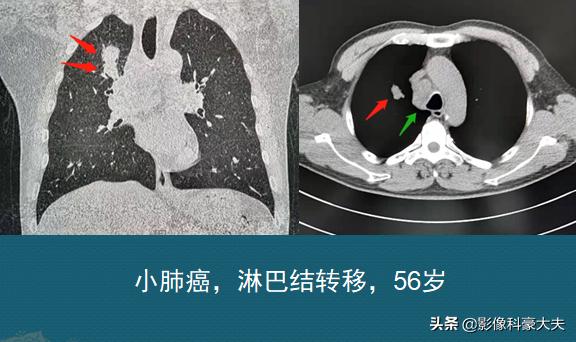

这位病人才56岁,右上肺癌,肿瘤虽然才2.5厘米,位置不太好,癌细胞像爬山虎一样,在边缘探出触手侵犯了肺门周围的肺间质,并通过这些通道发生了纵隔淋巴结转移……

第二位病人肿瘤差不多大小,有分叶,有胸膜牵拉,并发生了支气管截断,这个病人的癌细胞破坏力更大,沿着血液循环流窜到了腰椎椎体,建立起新的殖民地,形成了卵圆形骨转移瘤,从而让病人失去手术机会……

这两位都是病理确诊的肺腺癌病人,今天都是回来复查的,分别做过化疗和靶向治疗,目前控制得比较稳定,但都还不到1年,未来还不好说,只能祝福他们放下负担乐观面对!